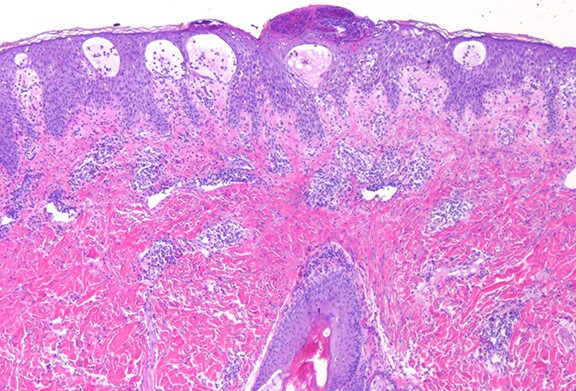

Xét nghiệm máu: thường thấy bạch cầu trung tính và các dấu hiệu viêm tăng cao. Có thể có tăng bạch cầu ái toan và bất thường về thận hoặc gan và cần được theo dõi.Sinh thiết da: mụn mủ dưới lớp sừng chứa đầy bạch cầu trung tính.Test áp: đôi khi được sử dụng để chẩn đoán nguyên nhân gây ra AGEP.